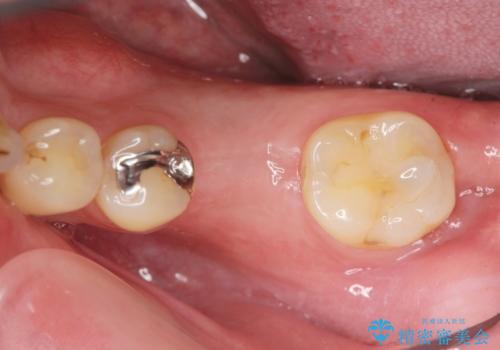

抜歯後、骨の再生を待ったことで、清掃性の高い位置に埋入を行い機能的・審美的なインプラント治療を行うことができました。